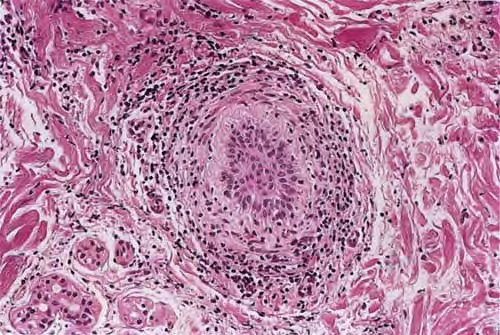

Histopathology.

The diagnostic pathologic feature is peribulbar lymphocytic inflammation (“swarm of bees”) affecting anagen follicles or follicles in early catagen. The inflammatory assault on anagen follicles induces a premature conversion to catagen . Consequently, the number of catagen and telogen follicles found may be marked, approaching 100% . Follicles may enter a persistent phase of telogen in which the hair shaft has already been shed, manifested by the telogen germinal unit .As follicles enter catagen, the lymphocytic infiltrate may persist around the epithelial remnant of the receding follicle and also within and surrounding the collapsed follicular sheaths. Telogen hairs show little to no perifollicular inflammation.